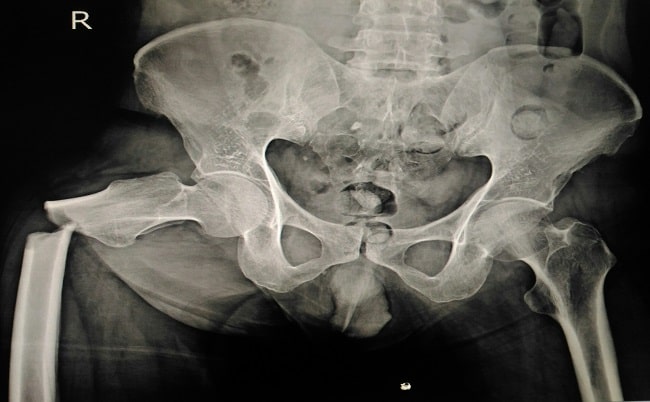

Fraktur femur ditandai dengan adanya nyeri pada paha, deformitas, dan krepitasi, dengan atau tanpa riwayat trauma sebelumnya. Pada pemeriksaan rontgen, bisa tampak adanya diskontinuitas os femoralis.[2,5,6]